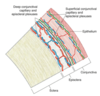

Quais as camdas histológicas da esclera?

Episclera

Estroma

Lâmina fusca

O que constitui a episclera?

Tecido conjuntivo fibrovascular - colágeno com distribuição circunferencial e adesão forte aos vasos

Além disso, existe tecido elástico, macrófagos e melanócitos

Como é a adesão das episclera à Tenon?

Forte próximo ao limbo e mais fraca em direção à região posterior

Qual os principais componentes do estroma da esclera?

Colágeno tipo I

Fibroblastos (baixa celularidade)

Proteoglicanos - Decorin e biglicano

GAGs e fibras elásticas